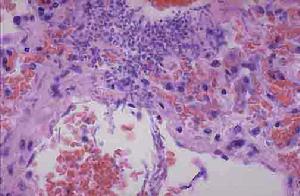

(二)發病機制病理檢查顯示在固有膜和腺周組織有非特異性炎症但這些變化亦見於正常對照組的前庭組織;其他病變有鱗狀上皮化生角化不全和非特異性補體與纖維蛋白沉積。形態學證據表明,外陰前庭黏膜的神經支配方式發生了結構上的改變上皮層神經纖維出芽勱,游離神經末梢增生對這些神經末梢內的神經肽含量檢測證實,降鈣素基因相關肽GCRP免疫反應陽性有部分學者用傷害感覺器的外周敏化理論來解釋外陰前庭炎的發病機制,即外陰前庭炎患者的感覺異常是由於不同類型的C傷害感受纖維末梢敏化和增生所致,即感受機械和熱刺激健康搜尋的多覺性C纖維、只對傷害性刺激敏感健康搜尋的C纖維甚至平時對任何刺激均健康搜尋不敏感的沉默silent纖維這些纖維敏化後,其傳入衝動增多而發生時間總和勱同時傷害感受纖維末梢數量的增多又可使傳入衝動發生空間總和最終導致痛閾降低。另外感覺異常也存在於外陰前庭患者健康搜尋的前庭前部黏膜儘管這部分黏膜並無紅斑勱推測此區域感覺異常也可能與傷害感覺器的外周過敏化有關。

外陰前庭綜合症細胞結構圖1.藥物治療局部套用1%氫化可勱的鬆軟膏,同時套用2%~5%的利多卡因溶液局部外塗以減輕性交不適對以上治療無效時或病變較重者健康搜尋可選用高效皮質激素如0.025%氟輕鬆或0.1%曲安奈德軟膏外用。其他治療如溫水坐浴性交前液狀石蠟潤滑前庭部。局部或肌內注射干擾素α有一定療效有效率為50%健康搜尋。有些病人使用抗組胺藥物有效。由於三環類抗抑鬱藥具有中樞鎮痛作用,同時對繼發抑鬱亦有效因此可以套用套用抗生素等療效健康搜尋不肯定如口服咪唑類抗真菌藥物甲硝唑均無效健康搜尋。